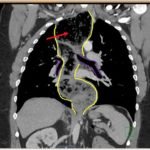

The chest X-ray demonstrated a markedly widened mediastinum (red brackets), raising concern for thoracic aortic aneurysm/aortic dissection, which prompted labs and contrast-enhanced computed tomography (CT) of the chest. The CT revealed a dilated proximal esophagus that narrowed distally (yellow tracing and red arrow), with particulate material, mass-effect on the trachea (purple outline), and bilateral patchy opacities suggesting aspiration. Barium esophagram showed a drastically dilated esophagus filled with contrast (yellow arrow), terminating into the classic “bird’s beak sign” (red arrow) at the lower esophageal sphincter (LES). Esophageal manometry later confirmed achalasia, proving that widened mediastina can have unexpected etiologies.